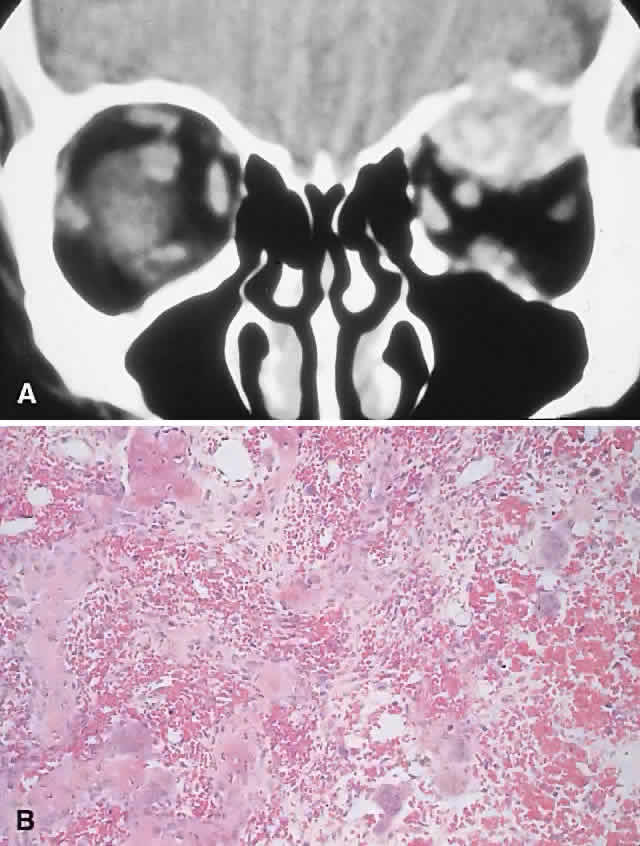

PRESENTATION. The site and the extent of disease are the major determinants of symptomatology. Facial asymmetry, proptosis, and globe displacement evolving over many years are the most common manifestations (Fig. 2). Nasolacrimal duct blockage, diplopia, nasal obstruction, malocclusion, raised intracranial pressure, and cranial nerve palsies also occur.25,28–30 Acute or subacute compressive optic neuropathy can arise as a result of intralesional hemorrhage, sphenoidal mucocele, or secondary aneurysmal bone cyst.31 A more chronic visual loss, although less commonly reported, may occur as a result of compression in the optic canal or at the chiasm. On occasion, a superimposed ischemic neuropathy in the context of chronic compression leads to an acute on chronic deterioration in vision.32

Fig. 2. A. A 20-year-old man presented with a longstanding history of left proptosis and facial asymmetry. B and C. Bone window CT scan showed extensive fibrous dysplasia involving the greater wing of the sphenoid in a sclerotic fashion and a more pagetoid appearance in the maxillary and ethmoidal regions. D and E. Dominant histologic features consisted of irregular trabeculae of woven bone in a fibrous stroma with minimal osteoblastic activity (E) surrounding the osteoid (hematoxylin-eosin; D × 20, E × 50).

IMAGING. In the craniofacial bones, fibrous dysplasia tends to expand the bone, with thinning of the overlying cortex. The margins are poorly defined, and the dysplasia transgresses suture lines; the proportion of mineralized to fibrous tissue determines the degree of radiolucency. Most cases demonstrate a relatively equal mixture, resulting in a pagetoid appearance. Where the fibrous element is predominant, there may be cystlike areas; a preponderance of mineralized tissue, however, results in a homogeneous, sclerotic, “ground-glass” picture. Fries34 reviewed 39 patients with fibrous dysplasia of the craniofacial bones and found a pagetoid pattern to be most common (56%), followed by sclerotic (23%) and cystlike (21%) appearances.

HISTOPATHOLOGY. Macroscopically, fibrous dysplasia consists of gritty, white-to-pink tissue, often with blood or serous-filled cystic areas. Histologically, there is a fibrous background containing trabeculae of woven bone. The stroma has variable amounts of collagen, fibroblasts, and vascularity. There may also be myxomatous areas and secondary aneurysmal bone cysts. The curvilinear bone trabeculae take on a variety of configurations, including C or Y shapes (so-called Chinese characters). These trabeculae sometimes have irregular margins as a result of the attachment of collagen fibers arising in the stroma. Cartilaginous nodules as well as small foci of lamellar bone are occasionally seen, but the vast majority of lesions contain immature woven bone. At its periphery, fibrous dysplasia permeates normal bone, and there may be areas of reactive bone with more prominent lamellar bone formation and osteoblastic rimming. Sequential biopsies of fibrous dysplasia from childhood to adult life have shown that the histologic picture does not change with time.36